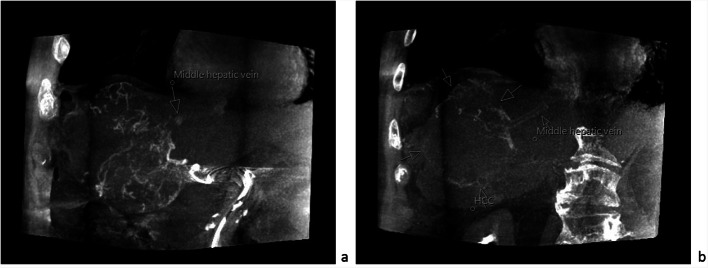

Aim: Prediction of posttreatment lung mean dose (LMD) during liver radioembolization (RE) work-up is essential for risk evaluation of radiation pneumonitis, especially when treating large hepatocellular carcinoma (HCC) where the chance of arteriovenous shunting is not negligible. In case of holmium-166-([166Ho])-RE, either [99mTc]TcMAA or 166Ho-microspheres can be used as scout tracers. Safety of use of 166Ho-scout has been demonstrated previously, but, to our notice, evaluation of lung radiation dose due to 166Ho-scout activity in case of significant lung shunting has not been described so far. Therefore, a retrospective study was conducted to evaluate the presence of pulmonary shunting in HCC patients influencing therapeutical approach and to assess lung 166Ho-scout dose in these patients.

Materials and methods: Twenty-nine HCC patients referred for RE were retrospectively evaluated. All work-ups were performed with 166Ho-microspheres. Scout imaging consisted of a hybrid SPECT/CT acquisition covering the thoraco-abdominal region. As mentioned in the manufacturer's instruction for use of 166Ho-microspheres, the possibility of > 30 Gy lung radiation exposure in a single treatment is withheld as contra-indication for RE. In patients with lung shunt resulting in predicted posttreatment LMD > 30 Gy, lung 166Ho-scout dose due to patient-specific injected activity was calculated, alongside two hypothetical scenarios: lung 166Ho-scout dose related to patient's lung shunt fraction (LSF) assuming administration of leaflet prescribed maximum 166Ho-scout activity and in case of 100% LSF according to patient-specific injected scout activity. Afterwards, these patients were followed for 3 months or till death.

Results: In the 29 patients, average predicted posttreatment LMD was 10.0 Gy (range 0.1-138.9 Gy), four of them revealing predicted LMD > 30 Gy. Based on patient-specific injected 166Ho-scout activity (range 100-200 MBq), average lung 166Ho-scout dose of 0.5 Gy (range 0.1-0.8 Gy) was calculated in these 4 patients. Assuming administration of leaflet prescribed maximum activity of 250 MBq, average lung 166Ho-scout dose would be 0.9 Gy (range 0.4-1.7 Gy). In case of a 100% LSF, average lung 166Ho-scout dose would be 2.2 Gy (range 1.5-2.7 Gy) due to patient-specific scout activity. In these 4 patients, RE was denied and alternative treatment was started. No pulmonary adverse events related to 166Ho-scout were recorded.

Conclusion: This study supports previous reports that 166Ho-scout is a safe alternative to [99mTc]TcMAA -scout and underlines the importance of predicting posttreatment LMD when treating large HCC since 13.8% of our patient group presented arteriovenous shunting with impact on treatment planning.